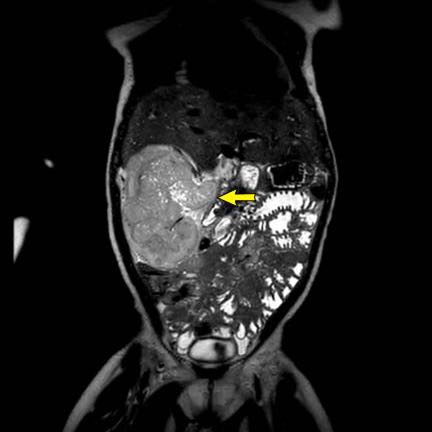

Ca lâm sàng 1

Hình ảnh chuỗi xung T2W mặt phẳng coronal cho thấy một khối u không đồng nhất ở thận trái với các thành phần nang nhỏ.

Khối u ngấm thuốc kém hơn so với phần nhu mô thận bình thường còn lại ở ngoại vi.

Các thành phần đặc của khối u cho thấy hạn chế khuếch tán rõ rệt (mũi tên).

Đây là u Wilms ở bé trai năm tuổi. Hóa trị tiền phẫu được thực hiện theo phác đồ Umbrella của SIOP-RTSG, sau đó tiến hành cắt thận.